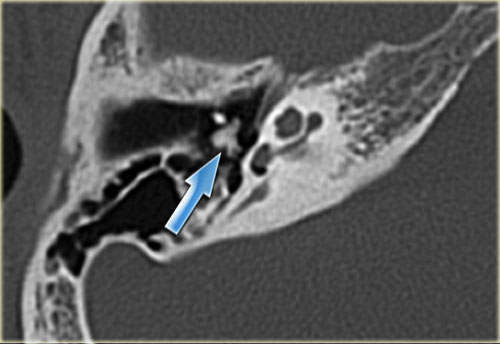

Bên trái là hình ảnh của một bệnh nhân nữ 40 tuổi với xương chũm xơ cứng.

Ống đá chũm được nhìn thấy rõ ràng. (mũi tên)

Bên trái là hình ảnh xương chũm thông bào tốt.

Ống đá chũm khó phân biệt (mũi tên).